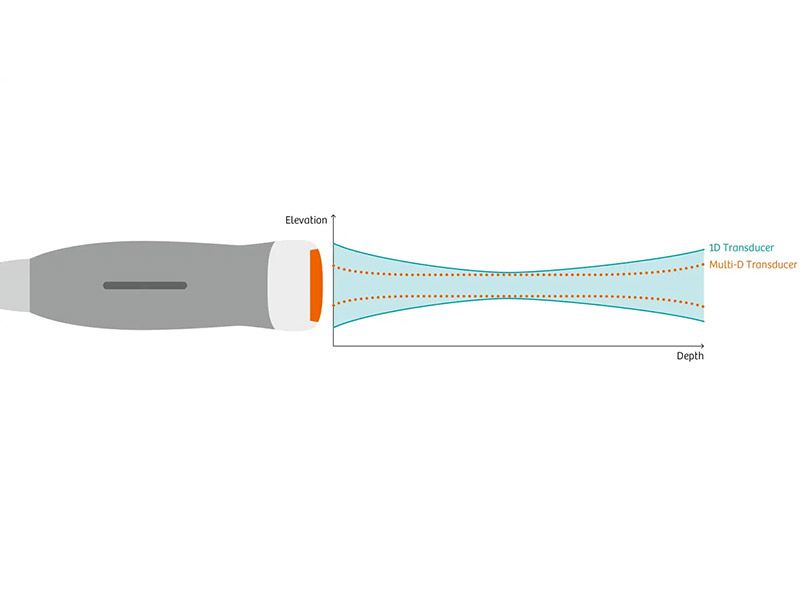

I trasduttori ad alta densità di elementi con tecnologia Multi-D consentono il controllo dinamico del FOV e di mantenere un’ottima risoluzione di contrasto fino a 40cm di profondità